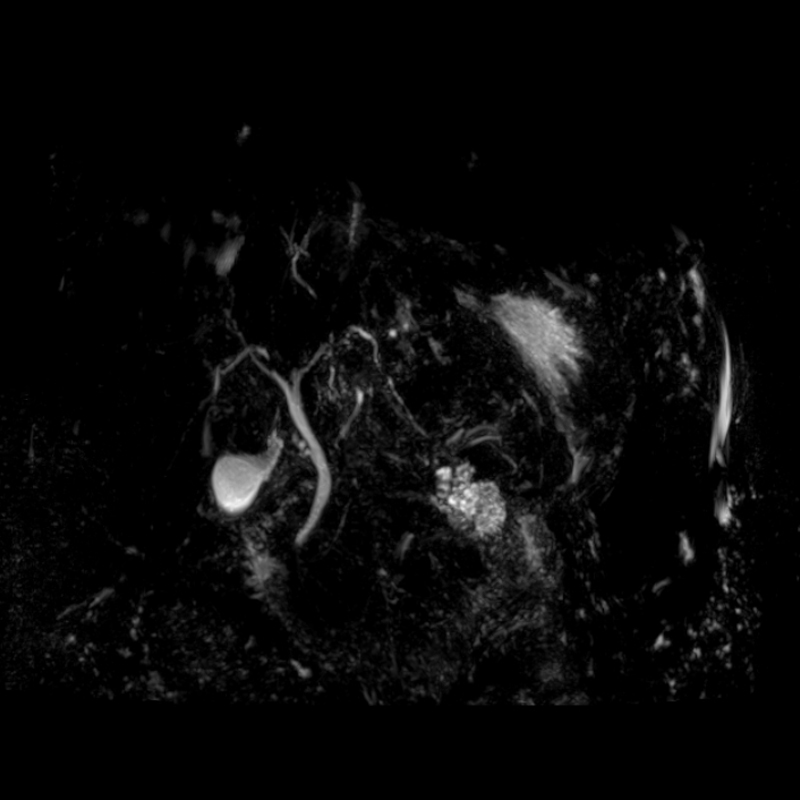

3 Tesla MR Tüm Vücut Görüntülemede Yapay Zeka Destekli Son Teknoloji